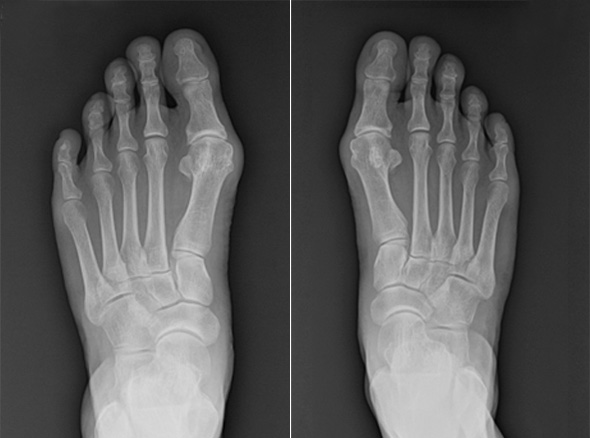

MICA, minimally invasive Chevron & Akin osteotomy

이전에는 무지외반 수술은 5cm 이상 피부를 절개하고 뼈를 싸고 있는 골막을 절개하여 수술을 하였습니다.

그래서 무지외반 수술은 통증이 심한 수술에 속하였지만

비절개 무지외반 교정술을 시행하고 나서는 획기적으로 회복 속도가 빨라졌고,

골막을 절개하지 않기 때문에 수술 후 통증도 많이 줄었습니다.

비절개 무지외반 교정술은 나사와 절골침이 들어갈 정도의 작은 구멍만 내고 하는 수술로 흉터는 낫고 나서는

거의 점처럼 보입니다. 수술 다음 날부터 큰 통증 없이 딛고 걸어 다니는 것도 가능합니다.